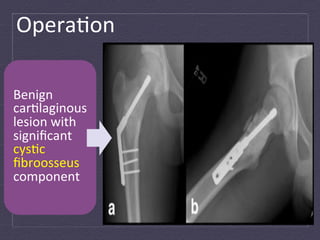

Opera:on   Benign   car:laginous   lesion  with   significant   cys:c   fibroosseus   component

Lobular  car:laginous  prolifera:on  without  significant  atypia   encircled  by  a  rim  of  bone.   Blood-­‐filled  cys:c  spaces  lined  by  benign  spindle  cells,  giant   cells,  woven  bone,  and  hemosiderin.   Focal  area  with  eosinophilic  “cementum-­‐like”  fibrin  reminiscent.